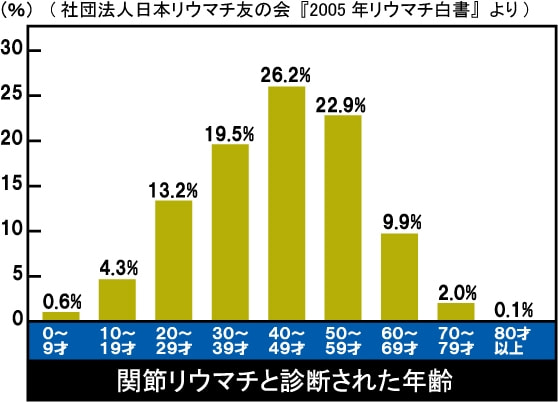

日本には約70〜100万人の患者さんがいるとされ、

女性に多く、30〜50代で発症するケースが目立ちます。

つまり、仕事や子育ての真っ最中に発症することも少なくないのです。